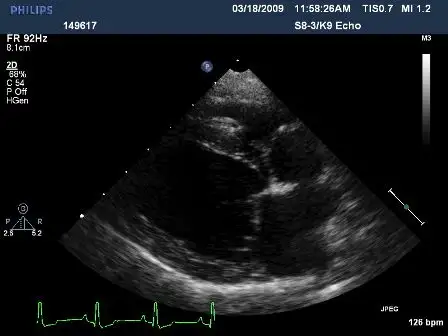

Although a diagnosis of MVD can frequently be based on signalment and murmur, evaluation of the severity of regurgitation should include thoracic radiography, echocardiography, or both.

Right lateral (Figures 1 and 2) and dorsoventral (Figures 3 and 4) radiographs of 2 dogs with grade 3/6, holosystolic, left apical murmurs. Dog 1 (Figures 1 and 3) has mild left atrial enlargement; dog 2 (Figures 2 and 4) has a severely enlarged left atrium.